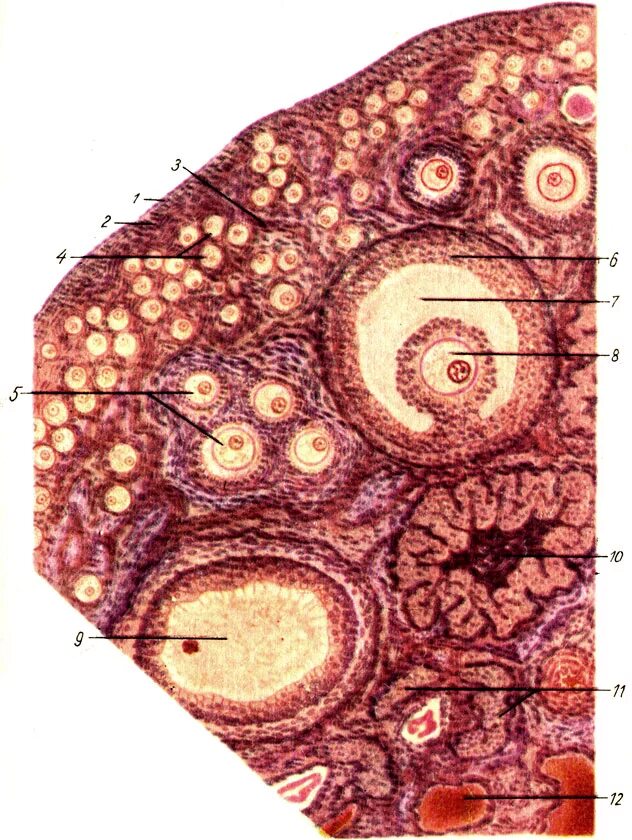

Сколько должно быть фолликулов в срезе